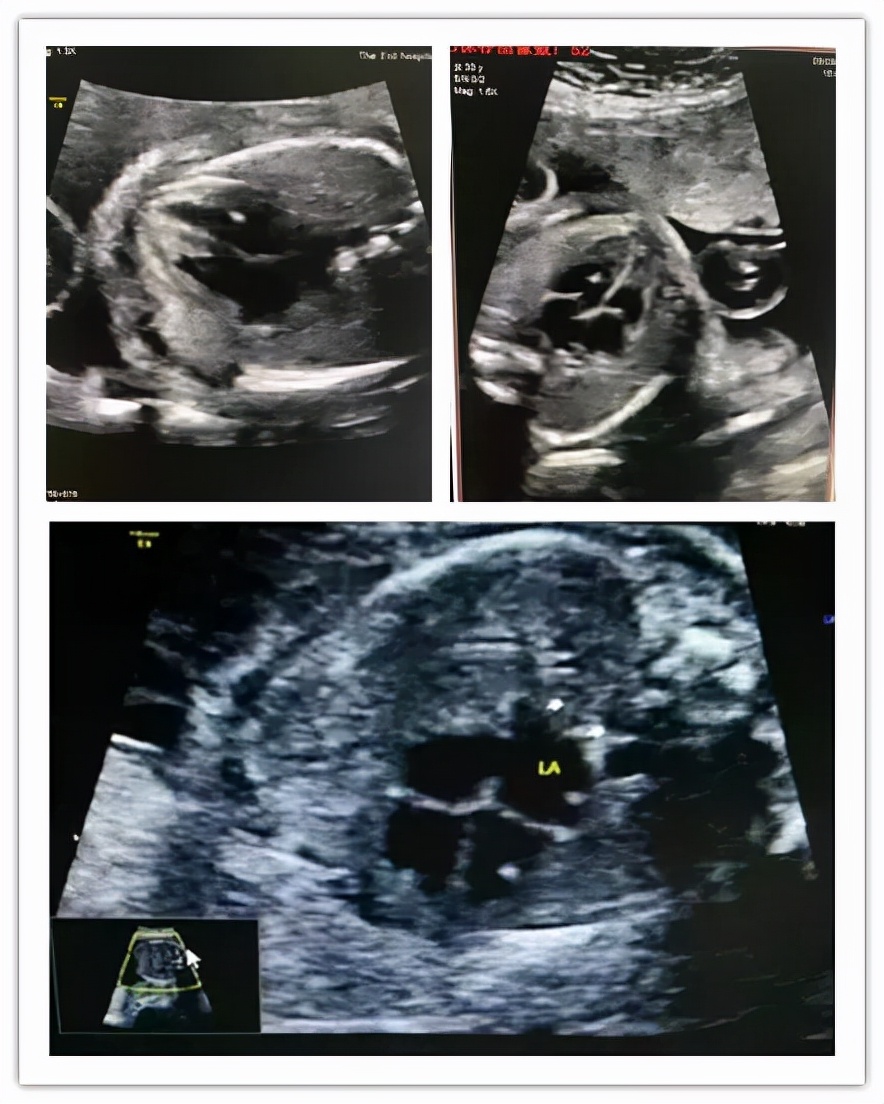

胎儿心室内点状强回声是一个声像图表现而不是一种心脏畸形,更不是一种心脏异常诊断。

临床中,左心室强光点的几率多于右心室,也可同时见于两个心室,大部分显示为单个,少数显示多个,一般径线在1-6mm之间,位于乳头肌或腱索附近,随着妊娠月份的增加,多数强回声点渐渐模糊不清、缩小、甚至消失;少数可一直存在、直至分娩,甚至产后超声仍能观察到。对于大部分胎儿而言,心室内强回声点可能无重要的临床意义,单纯光点<5mm,一般是钙化现象,可以说这个强光点基本上可以说99%没问题的,孕妈们不用担心。因染色体变异而引起的强光点的可能只有0.5%~1%。